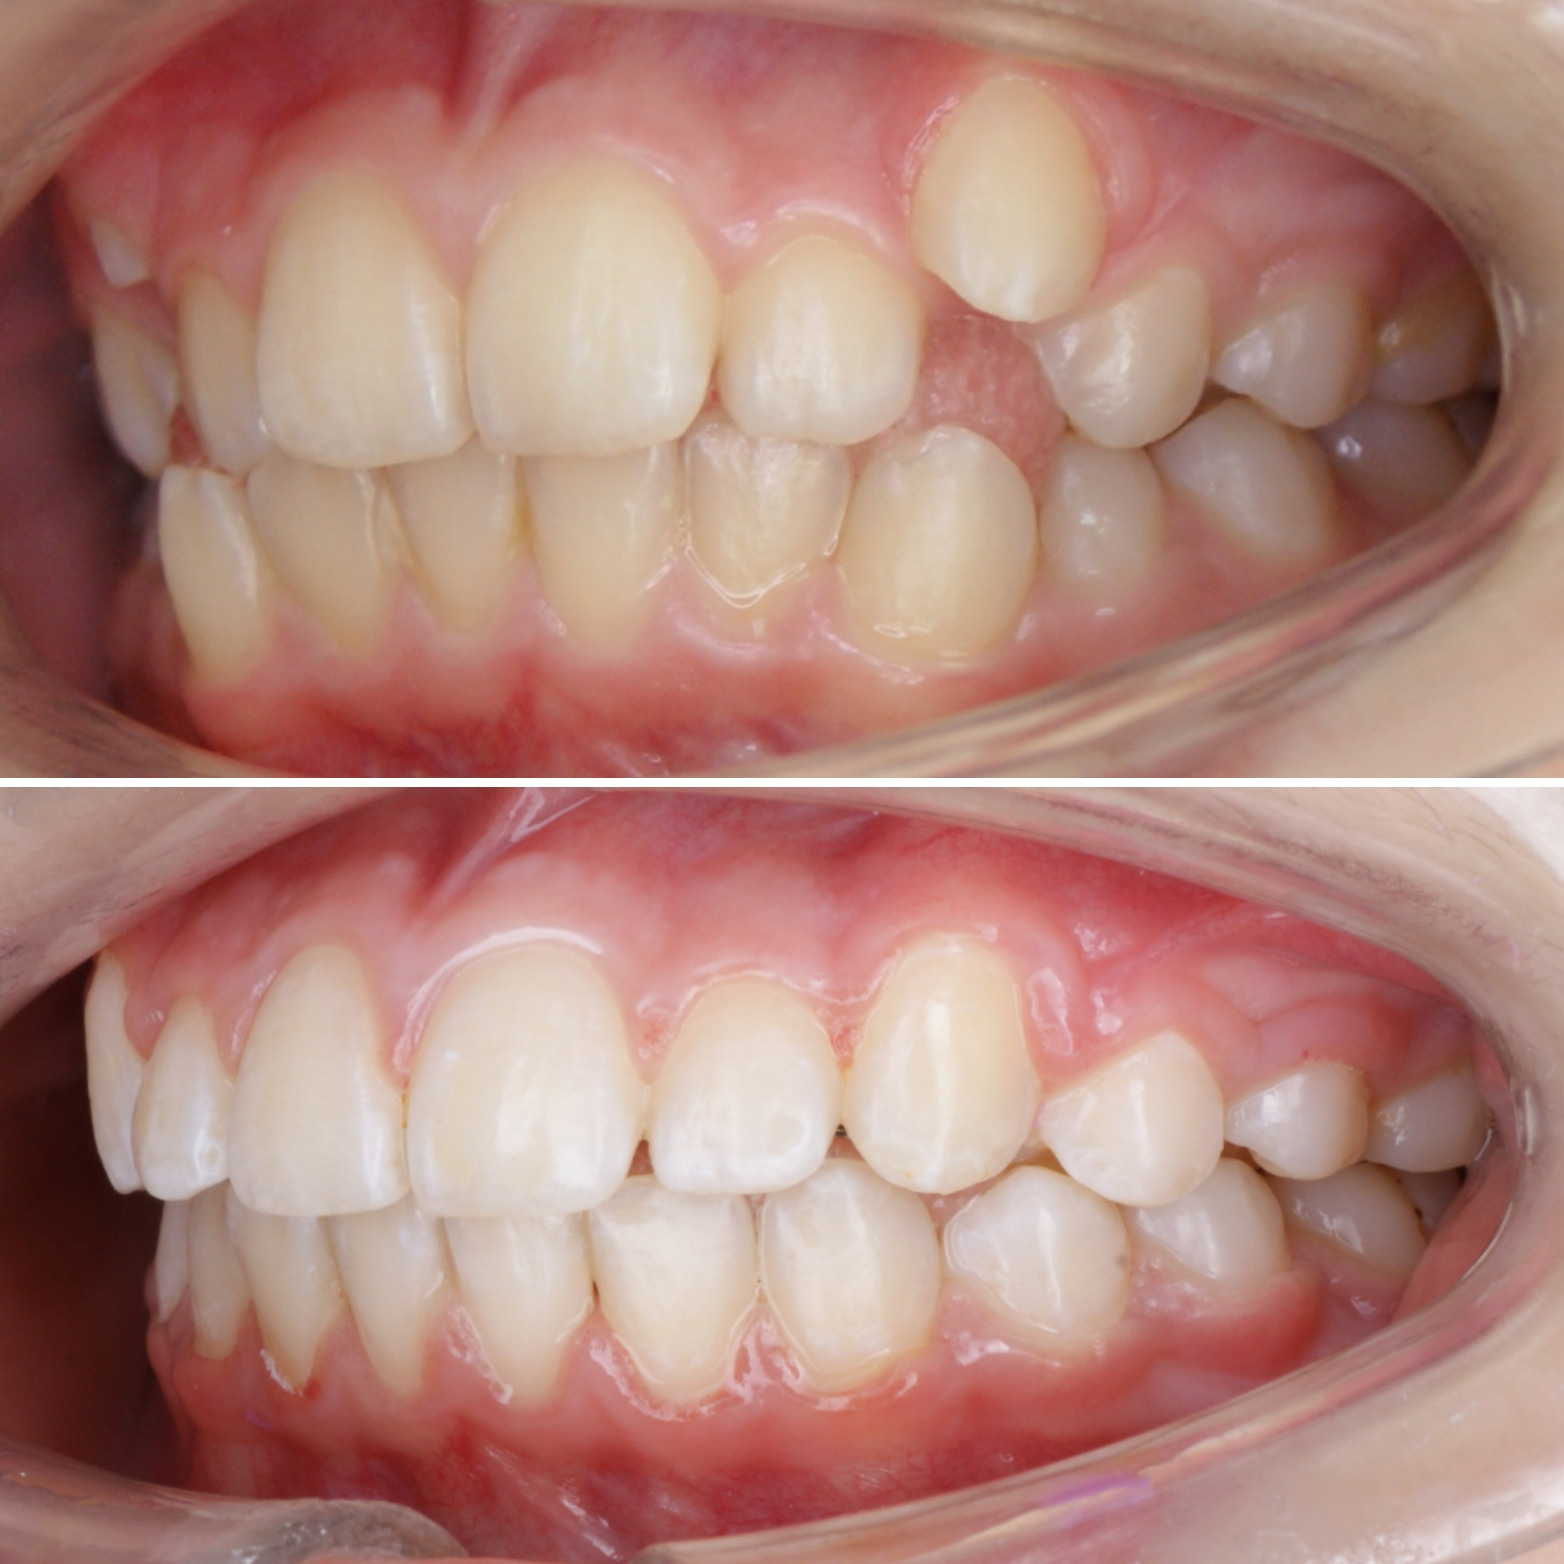

✔Глубокий прикус, дистальный прикус с пространством (щелью) между верхними и нижними резцами, скученное положение зубов, заблокированное нёбное положение верхнего левого зуба ✔Лечение на металлической самолигирующей системе Damon

✔Пациент, 12,5 лет на момент старта ✔Общий срок лечения 18 месяцев ✔Брекеты Damon Q ✔Дистальный, перекрестный, глубокий прикус, смещение нижней челюсти, несоответствие средних линий и сужение зубных рядов, скученность зубов, недостаток места для верхних клыков